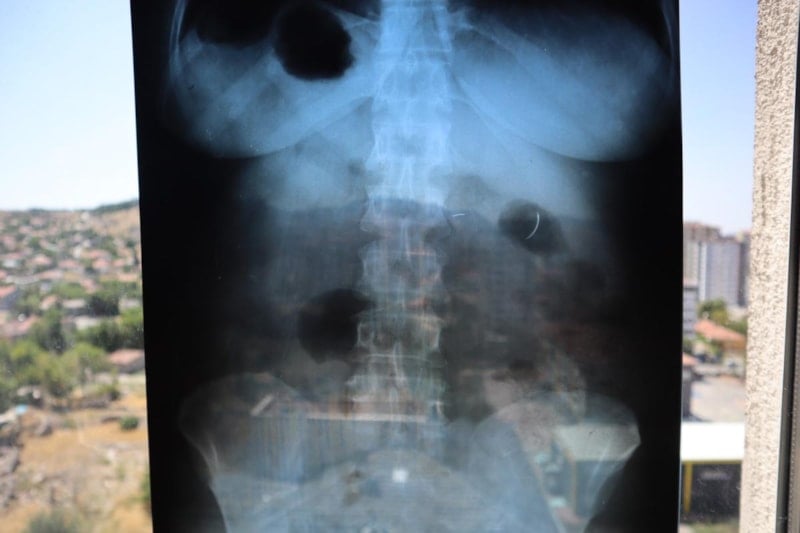

Ameliyat olduktan 6 yıl sonra böbrek rahatsızlığı nedeniyle hastaneye giden Tanyıldız’ın çekilen röntgeninde iğne görüldü.

Tanyıldız’ın kist ameliyatı sırasında karnında ameliyat iğnesi unutulduğu ortaya çıktı.

22 yıldır ameliyat iğnesiyle yaşayan Tanyıldız, "2003 yılında ameliyatım yapıldı. Karaciğerimdeki kistten dolayı ameliyat oldum. Karaciğerimde kist oluşmuş. Kisti alırken ameliyat iğnesini unutmuşlar. 6 yıl sonra fark ettim.

İlk öğrendiğimde başka doktora gittim, böbreklerimden rahatsızlanmıştım. Doktor film çekince ‘sen MR’a girme, ciğerinde iğne var’ dedi. O zaman fark ettim. Fiziksel olarak hala ağrısını, yıllardır çekiyorum" diye konuştu.

İğne 22 yıldır çıkarılmadı. Riskli olduğu için çıkaramıyorlar. Kanamayı durduramayacakları için, iğne ciğerimde geziyor. Açınca iğneyi bulamayacakları için, kimse o riski almak istemiyor. İnşallah bir doktor çıkar. Beni bu sıkıntıdan, 22 yıllık çektiğim çilelerden kurtarırsa çok mutlu olurum, dua ederim.